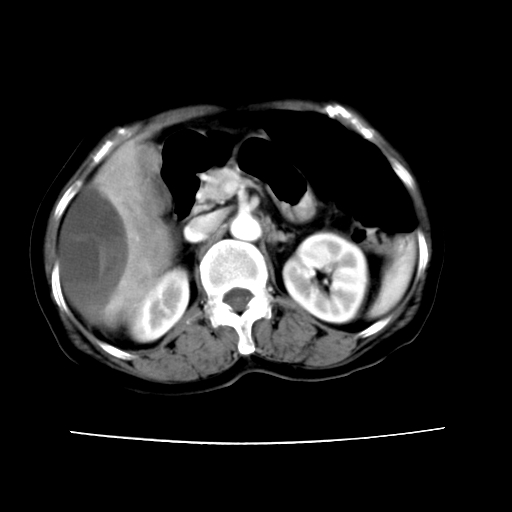

2008-11-10ct平扫(其间去中山医院诊治未行特殊治疗)

2008-11-10ct平扫见并肝内、血膜下血肿基本吸收,肝内低密度灶缩小。此时再做增强ct应有显着意义。对患者/医者都好!

从平扫+增强及治疗后复查片,病变明显缩小,不考虑肝癌出血可能,还是考虑为良性病变可能性大;单纯血肿并包膜下积液吧,病变强化没法解释,肝血管破裂出血吧,增强不符合典型血管瘤的表现,良性肿瘤破裂出血吧,复查片看来好像也不太支持(没做强化也不太好说)。本人还是考虑单纯肝内血肿并包膜下积液,强化是不是血管有外渗。

患者自6月至11月,如果是肝癌,没有经过特殊治疗,想必应该会有所进展吧,而不是ct所见,反而似有病灶减小的趋势。建议增强。